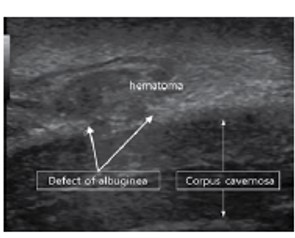

그림 12. 음경골절

음경골절은 병력 청취와 진찰만으로 진단이 가능하다. 초음파에서는 파열에 따른 출혈로 발생한 혈종이 저에코성 병변으로 관찰되며, 백막의 파열로 고에코성으로 나타나는 백막의 단절이 관찰된다(그림 12). 음경해면체 내의 동정맥기형은 주로 손상에 의해 발생하며 고혈류성 지속발기증을 유발한다. 칼라도플러 초음파로 arteriovenous 또는 arteriosinusoidal fistula를 관찰할 수 있다.